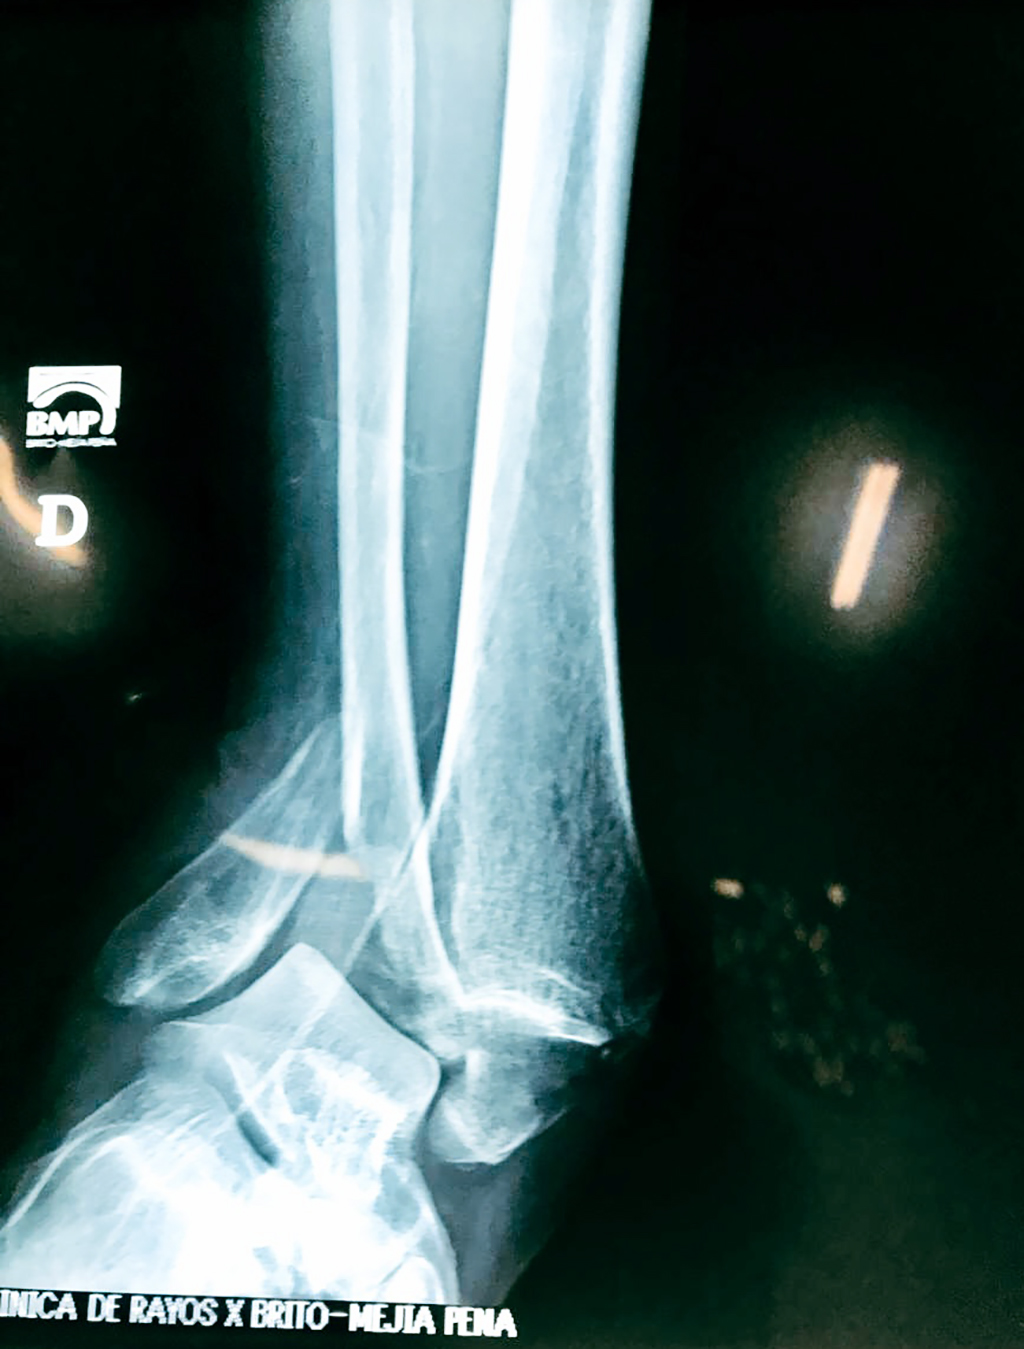

Una fractura de tobillo es la rotura de uno o más de los huesos del tobillo. Estas fracturas pueden ser:

- Parciales (el hueso está sólo parcialmente fisurado, no del todo).

- Completas (el hueso está perforado y está en 2 partes).

- Producirse en uno o ambos lados del tobillo.